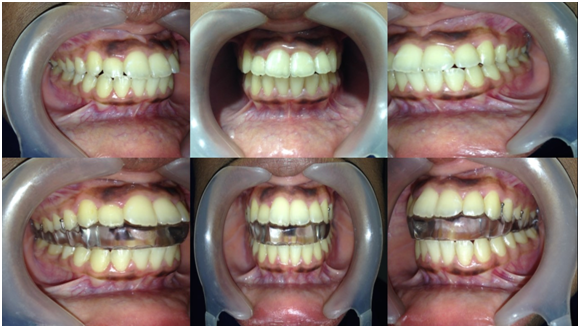

Hegab TMJ Splint (HTS) is Maxillary full-arch hard stabilization splints fabricated with fluid resin. The splint attached to the upper jaw using ball clasps without any extensions of the acrylic resin on the buccal or labial surface of the upper jaw. The retention of the splint to the upper jaw is coming only from the ball clasps. The occlusal splint has indentations on its occlusal surface to guide and hold the mandible in centric relation (Figure 1). The occlusal splint vertical thickness of 4 mm used for treatment of the cases with disk displacement with reduction (DDR-HTS4). While for cases of disk displacement without reduction, 6 mm vertical thickness of the occlusal splint was selected (DDNR-HTS6). The vertical thickness of the occlusal splint was measured at the molar area and the indentations help to achieve the Simultaneous equal contacts on all teeth (Figure 2). The selection of the vertical thickness of the occlusal splint based on evidence based study using the MRI to evaluate the movement changes within the TMJ with different splint thickness.4

Figure 1 Hegab TMJ Splint (HTS).

Figure 2 intraoral lateral and frontal view of the Hegab TMJ Splint (HTS).